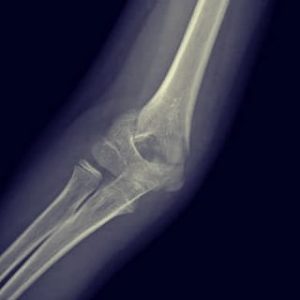

- Fracturas de codo

- Fractura supracondílea

Fractura supracondílea de humero